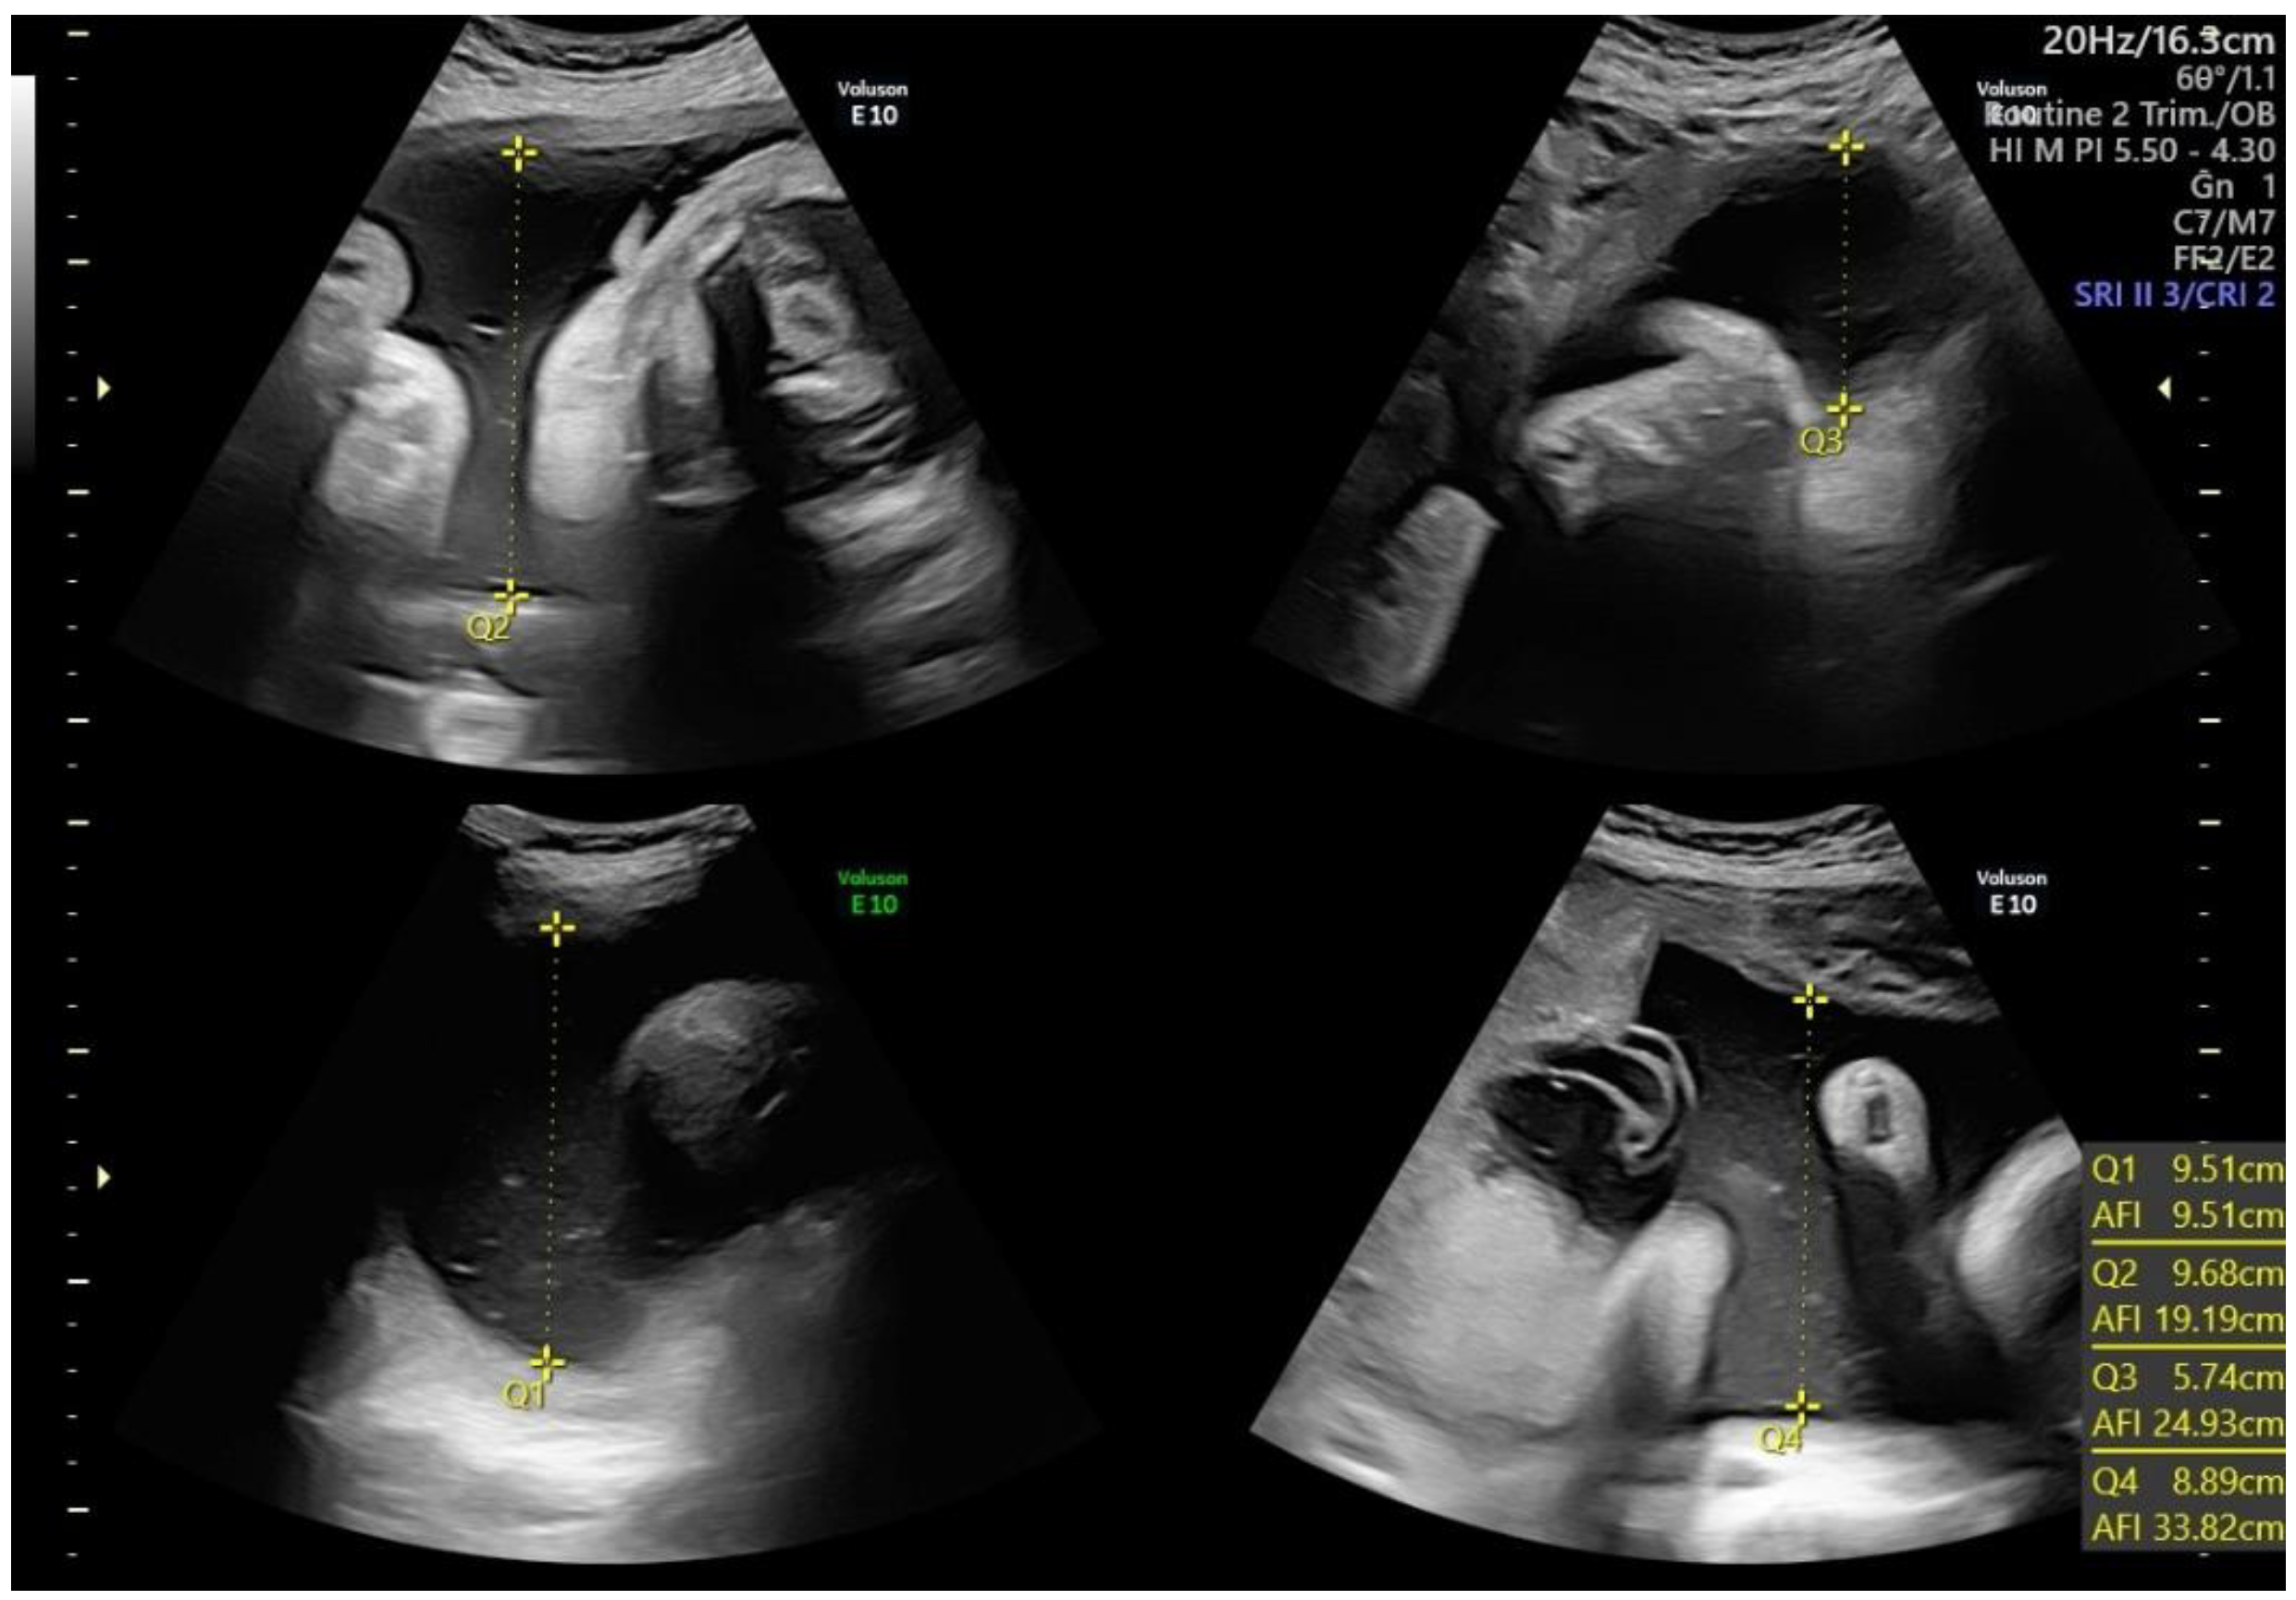

Polyhydramnios, or hydramnios, consists of an excess of AF (Figure 3). Polyhydramnios can be diagnosed by either an SDVP ≥ 8 cm, or an AFI ≥ 24 cm or 25 cm (depending on whether the 95th or 97th percentile is used). The prevalence of polyhydramnios is 1–2% of singleton pregnancies [52,53]. The degree of polyhydramnios is frequently categorized as mild, moderate, or severe [18] depending on the value of AFI or SDVP, as shown in Table 2. Polyhydramnios may be further classified as transient, when it resolves spontaneously through gestation, or persistent [54].

Figure 3.

Polyhydramnios. Q: quadrant. AFI: Amniotic Fluid Index.